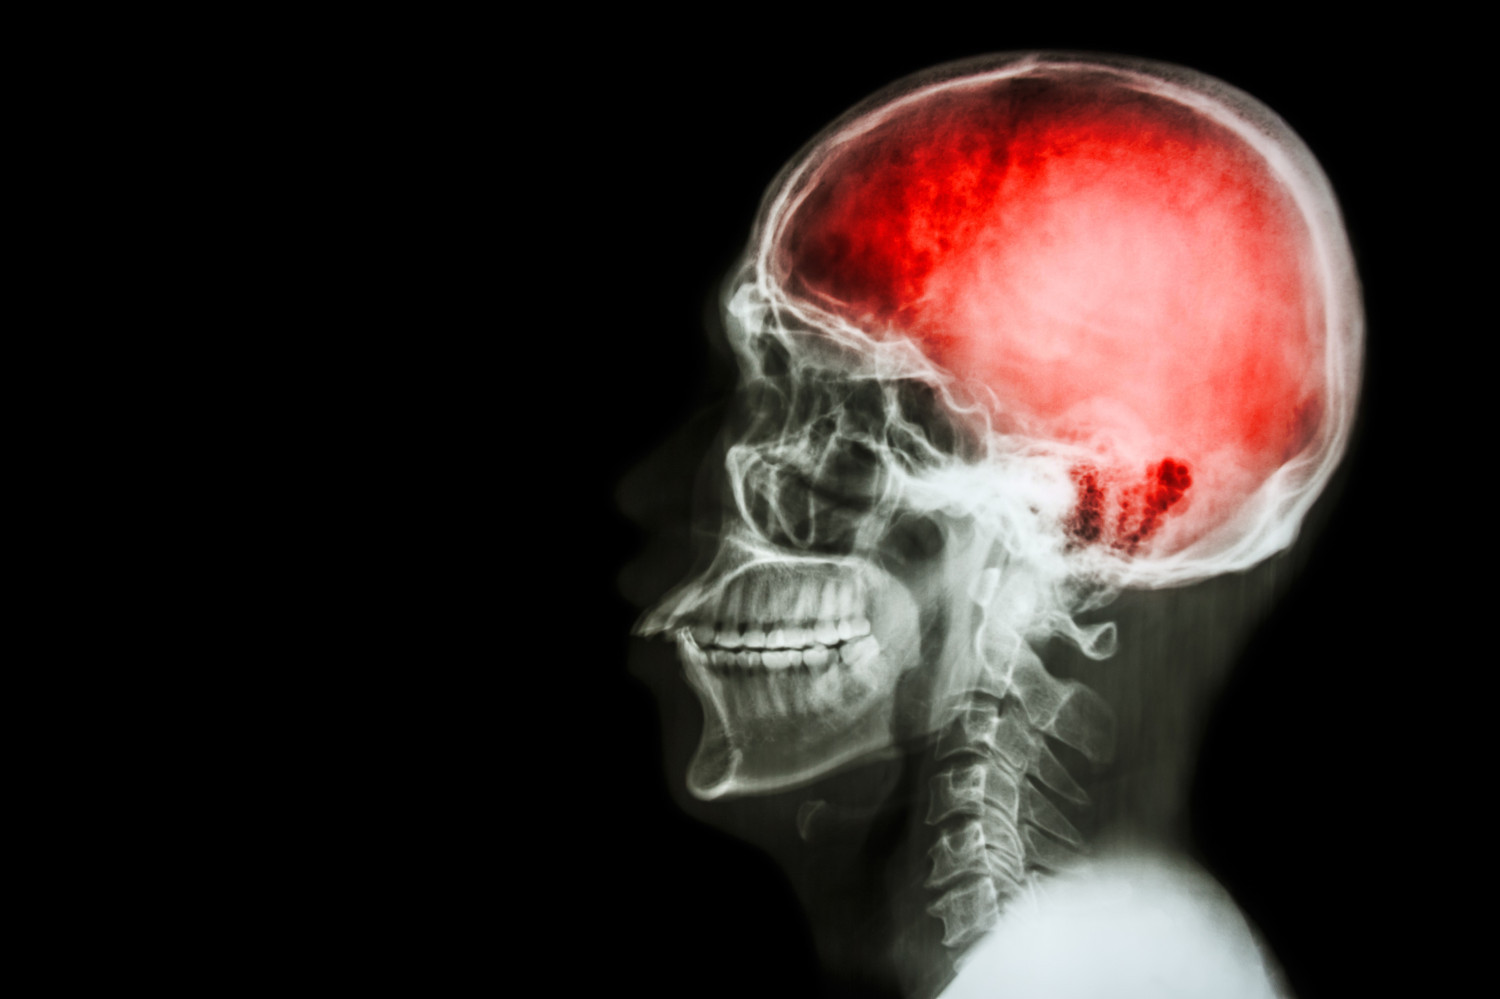

Прием эдоксабана не предотвращал повторный инсульт

Частота развития комбинированного показателя, включавшего инсульт, системную эмболию и сердечно-сосудистую смерть, на фоне приема эдоксабана и при отсутствии антикоагулянтов существенно не отличалась и составила 11,5 и 12,2% соответственно. При пересчете на пациенто-года эти показатели составили 5,7 против 6,3%.

Частота повторных инсультов также оказалась сопоставима в группах эдоксабана и отсутствия антикоагулянтов — 3,3 против 4,6%. В каждой группе диагностировали восемь смертей от сердечно-сосудистых заболеваний.

У пациентов в группе приема антикоагулянтов частота развития массивного кровотечения оказалась выше в четыре раза — восемь случаев против двух случаев в контрольной группе.

| Анализировали данные 253 пациентов, которые перенесли инсульт или транзиторную ишемическую атаку и у которых выявили фибрилляцию предсердий. Из них 122 участника получали эдоксабан, а 131 участник не получал антикоагулянты. Оценивали частоту повторных инсультов и массивных кровотечений. |

Авторы заключили, что прием пероральных антикоагулянтов (в частности, эдоксабана) не приводил к заметному снижению риска повторного инсульта, но значительно увеличивал риск кровотечений.